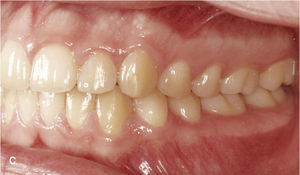

Corrección de mordida cruzadaLas mordidas cruzadas se pueden tratar con el sistema Invisalign de forma muy predecible. La corrección de la mordida cruzada posterior se puede llevar a cabo con el sistema Invisalign exclusivamente o bien combinándolo con un tratamiento previo con botones y elásticos entrecruzados. La figura 11a muestra una oclusión clase II con mordida cruzada de los dientes 16 y 46. El tratamiento con Invisalign incluyó la distalización en la arcada superior derecha con corrección de la mordida cruzada mediante expansión transversal en la región del 16. La figura 11b muestra la situación intraoral a la finalización del tratamiento con configuración de una relación clase I y de una oclusión funcional de la región molar.